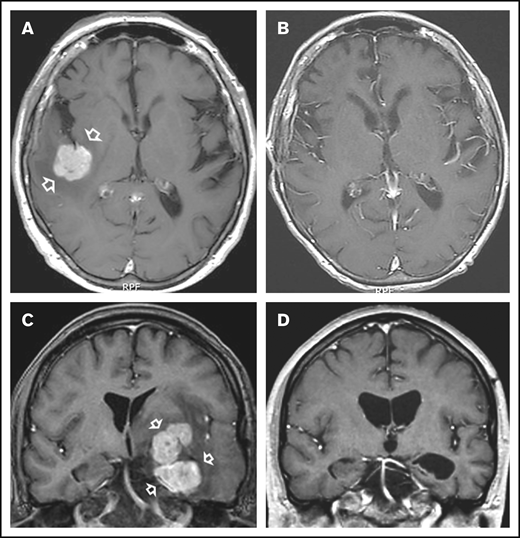

In all, 11 patients who received NGR-hTNF/R-CHOP had CR (examples in Figure 1) and 10 patients had PR, with an ORR of 75% (95% confidence interval, 59%-91%); 7 patients experienced PD. Thus, the predetermined activity threshold of ≥12 responses was largely achieved. The best response was achieved after the second course in 14 patients and after the fourth course in 7 patients. Responses were equally distributed in analyzed subgroups according to IELSG risk variables, site and number of lesions, previous therapies, and refractoriness (supplemental Table 3). Two of the 3 patients with intraocular disease achieved tumor regression at that site that lasted 3+ and 28+ months, respectively. Response lasted more than 6 months in all patients with CR (median, 11 months; range, 6-25+ months).

Examples of responses to R-CHOP preceded by NGR-hTNF. (A) Gadolinium-enhanced T1-weighted scan shows a large homogeneous enhancing lesion in the right parietal lobe (arrows) in a 65-year-old man at second relapse after high-dose methotrexate and after salvage high-dose ifosfamide-based therapy plus WBRT. (B) Tumor regression after 4 courses of experimental treatment. (C) Gadolinium-enhanced T1-weighted scan shows a large polylobate, enhancing lesion infiltrating the basal ganglia, diencephalon, and left temporal lobe (arrows) in a 39-year-old man with PCNSL refractory to previous high-dose methotrexate-based chemoimmunotherapy. (D) Tumor regression after 4 courses of experimental treatment.